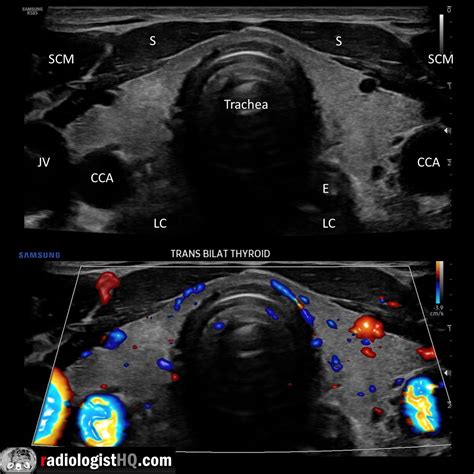

The Longus Colli muscle is a deep cervical flexor, meaning it is situated close to the bone and works to stabilize the neck rather than produce large, powerful movements like the trapezius or sternocleidomastoid. It is anatomically divided into three distinct parts: a superior oblique portion, an inferior oblique portion, and a vertical portion.

Because of its deep location, it acts as a primary stabilizer, acting much like a "corset" for the cervical spine. Its primary roles include:

• Stabilization: It supports the natural curvature of the neck, preventing the vertebrae from shifting under load.

• Cervical Flexion: It assists in nodding the head and bending the neck forward.

• Proprioception: It provides critical sensory feedback to the brain regarding the position of the neck in space.